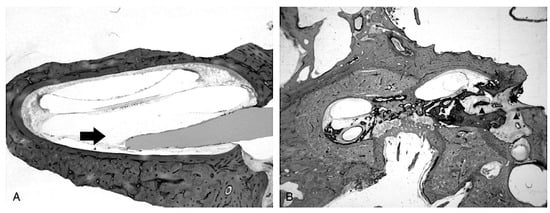

| Ishiyama et al. [20] | 13 HTB with translocation 6 with localized cochlear damage and 7 with translocation and lateral wall damage | Translocation with lateral wall injury (n = 7) was associated with lower SGN counts, poorer speech performance, and more abundant new tissue formation than localized translocation (n = 6). In 6/7, there was severe hydrops. All 7 had placement by cochleostomy with relatively longer electrode. Translocation tended to occur at about 180°. |

| Knoll et al. [21] | 19 HTB with translocation | Average angle of translocation was 159.2° which was associated with fibroosseous changes and lower SGN counts |

- Ishiyama, A.; Ishiyama, G.; Lopez, I.A.; Linthicum, F.H. Temporal bone histopathology of first-generation cochlear implant electrode translocation. Otol. Neurotol. 2019, 40, e581–e591. [Google Scholar] [CrossRef]

- Knoll, R.M.; Trakimas, D.R.; Wu, M.J.; Lubner, R.J.; Nadol, J.B., Jr.; Ishiyama, A.; Santos, F.; Jung, D.H.; Remenschneider, A.K.; Kozin, E.D. Intracochlear new fibro-ossification and neuronal degeneration following cochlear implant electrode translocation: Long-term histopathological findings in humans. Otol. Neurotol. 2022, 43, e153–e164. [Google Scholar] [CrossRef] [PubMed]